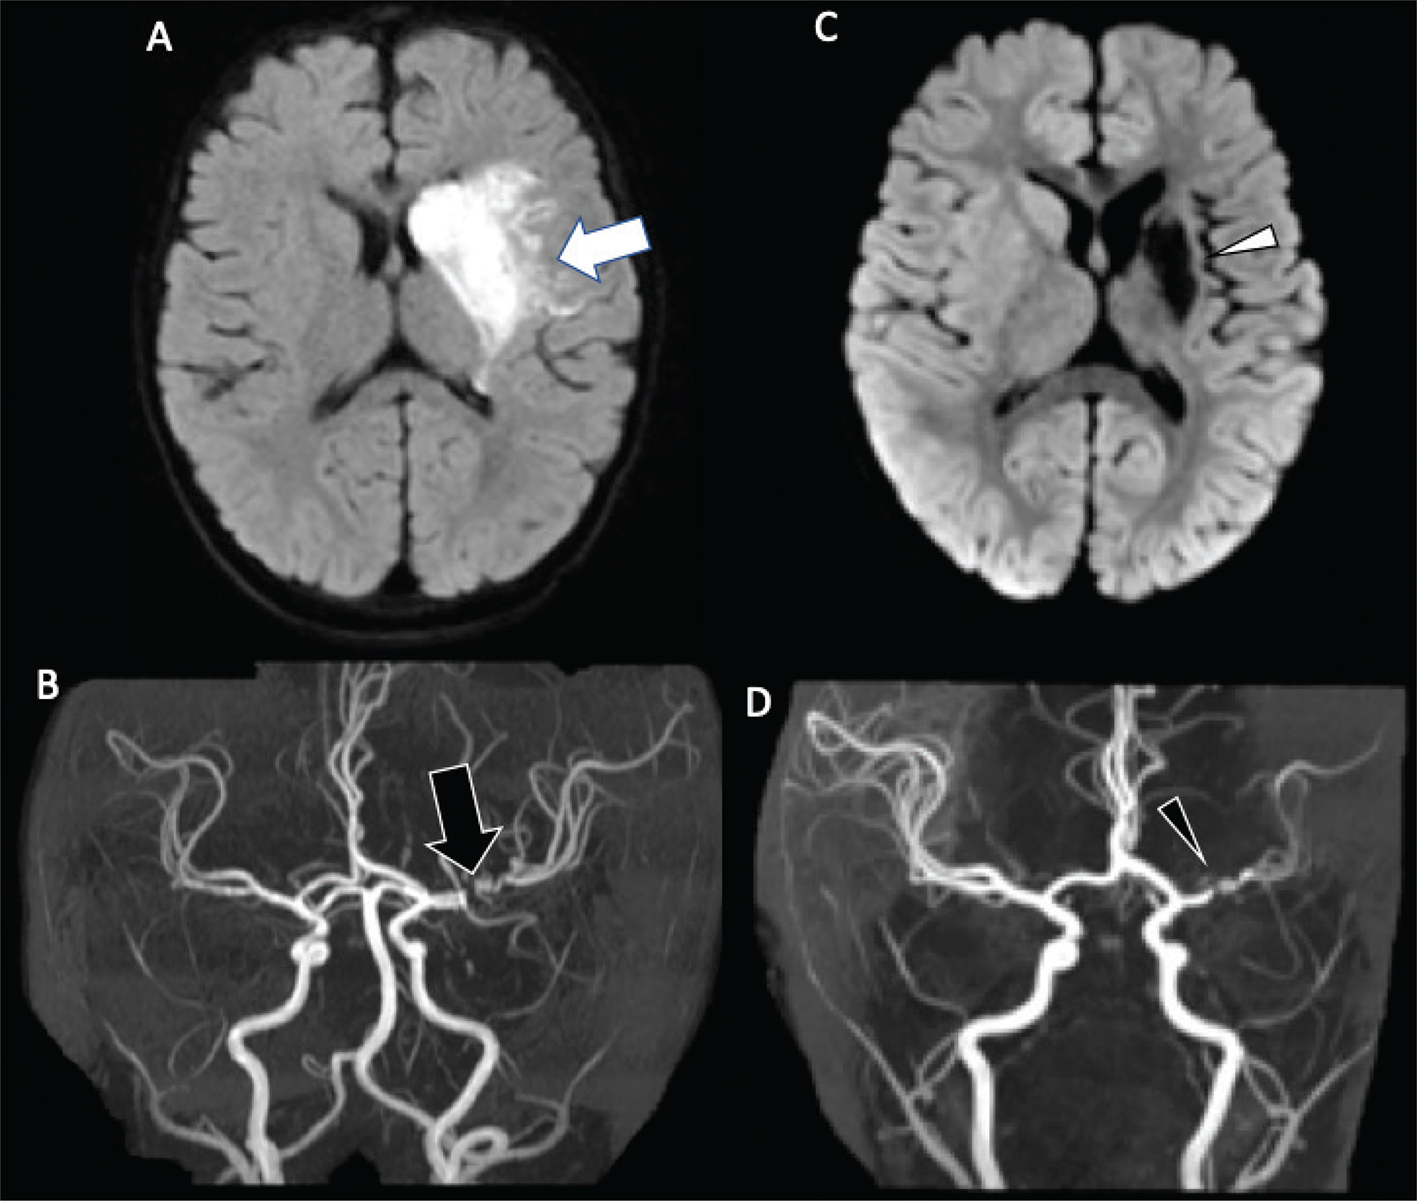

MRA can help define the site of stenosis, helping narrow the diagnosis in patients with arteriopathy, or identify a large vessel occlusion (Figure 4) (17, 23, 95, 96). A “banding” pattern is considered a pathognomonic feature for FCA-i but is less commonly identified by CTA or MRA than catheter angiography, presenting in less than one-quarter of cases, and is therefore specific but not sensitive for the diagnosis (Figure 5) (30). If arteriopathy is suspected and MRA is equivocal, vessel wall imaging, utilizing black-blood, T1-weighted volumetric imaging after gadolinium can demonstrate abnormal vessel wall enhancement in the setting of active inflammatory processes, as well as assess for intracranial arterial dissection on pre-contrast T1-weighted imaging (69). Between 64% and 74% of arterial defects in pediatric ischemic infarctions are located in the supraclinoid carotid artery or M1 segment of the middle cerebral artery (70). Stenosis in FCA may change in appearance over the short term. Over the long term, they usually normalize (~25%), stabilize after improvement (32%), or stabilize (45%) without further infarctions (23, 24). Outcome is better in patients in whom the arteriopathy stabilizes or improves than in those in whom it progresses, with a high risk of recurrent stroke in the latter population, approaching 25% within 1 year (17, 24). Some genetic arteriopathies have unique imaging appearances, such as ACTA2 mutation, which demonstrates dilation of the proximal internal carotid arteries, occlusion or narrowing of the distal internal carotid arteries, straight “broomstick-like” arteries of the circle of Willis, and absence of lenticulostriate collaterals (Figure 6) (34).

Fig 5

Figure 5. A 13-year-old previously healthy female who presented with new left-sided facial weakness. Diffusion weighted image (A) demonstrate acute infarcts in the right middle cerebral artery (MCA) territory (black arrows). Time-of-Flight MRA (B) shows stenosis of the proximal right M1 MCA segment (white arrowhead). Vessel wall imaging (C) demonstrates a cuff of enhancement at the stenosis (white arrow). Digital subtraction angiography (D) demonstrates a focal arterial irregularity and banding (black arrowhead) resulting in mild stenosis, compatible with focal arteriopathy of a likely inflammatory nature.